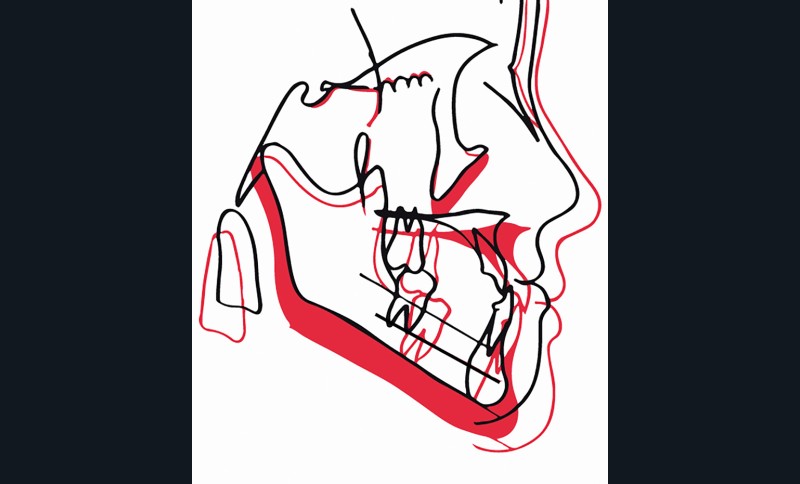

Si l’on analyse le résultat du point de vue squelettique, on constate une belle amélioration orthopédique du prémaxillaire, stable dans le temps. La croissance maxillaire a heureusement été toujours supérieure à la forte croissance mandibulaire. On note après orthopédie un bon support osseux pour la lèvre supérieure qui présente une meilleure épaisseur. À la fin de la croissance, les courbures naso-labiale et labio-mentonnière sont optimisées (fig. 5).

Les téléradiographies de profil confirment la croissance du maxillaire avec une légère tendance rotationnelle antérieure et une avancée du point A de 8 mm. La croissance mandibulaire est homothétique sauf dans la région du point B où elle est freinée (fig. 6-7).